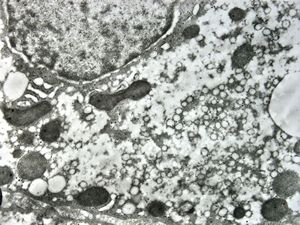

M,3y. | normal hepatocyte